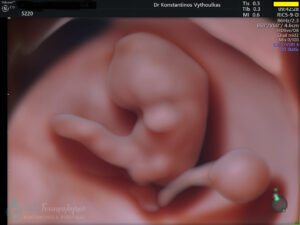

- Υπερηχογραφική εξέταση, η οποία συμβάλλει στη διαπίστωση της ενδομήτριας κύησης και αποκλεισμό της έκτοπης κύησης. Επιπλέον, μπορεί να διαπιστώσει εάν πρόκειται για μονήρη ή πολύδυμη κύηση, να ανιχνεύσει την εμβρυϊκή καρδιακή λειτουργία μετά τις 6 εβδομάδες και να προσδιορίσει υπερηχογραφικά την ηλικία κύησης, με βάση το κεφαλουραίο μήκος του εμβρύου μετά τις 8 εβδομάδες.